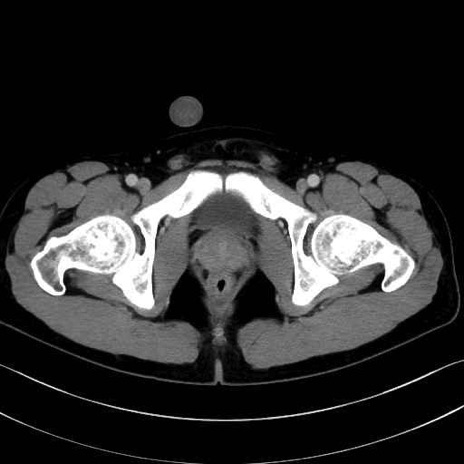

外閉鎖筋 (Obturator externus)